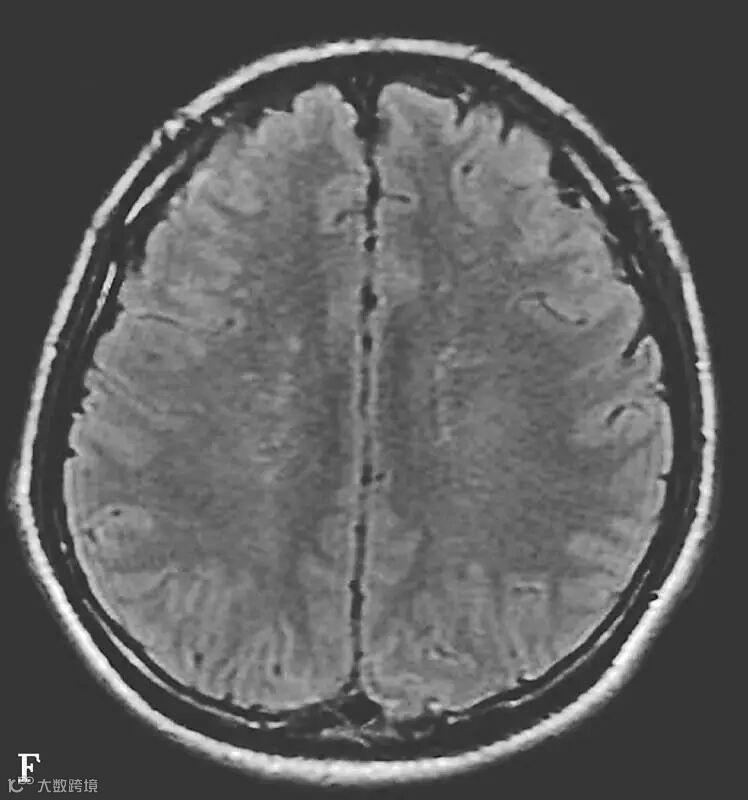

男,34岁,外伤后7天。A~H(A、B.T2WI,C、D.T1WI,E、F.T2WI-FLAIR,G、H.DWI):左侧岛叶及右侧顶叶白质可见斑片状稍长T1稍长T2信号,边缘不清,FLAIR及DWI呈高信号。双侧额部内板下可见新月形长T1长T2信号,FLAIR及DWI呈低信号。双侧顶枕部内板下可见弧形短T1长T2信号,FLAIR及DWI呈高信号

图6-11-2 弥漫性轴索损伤

男,36岁,外伤后2天。A~J(A、B.T2WI,C、D.T1WI,E、F.T2WI-FLAIR,G、H.DWI,I、J.ADC图):双侧额叶、半卵圆中心及胼胝体压部可见多发斑点状等T1稍长T2信号,边缘不清,FLAIR及DWI呈高信号,ADC图病灶信号减低 。